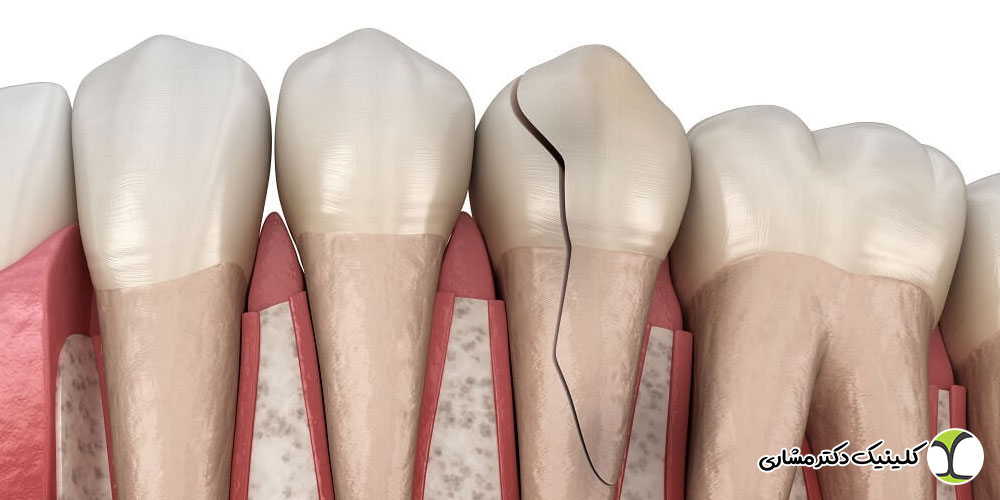

در این روش، دندانپزشک از مواد مخصوصی که رنگ و ظاهرشان شبیه دندان طبیعی است استفاده می کند تا شکاف بین دندان ها را پر کند و دندان ها صاف، یکدست و زیبا دیده شوند. برخلاف بعضی روش های دیگر، نیازی به تراش زیاد دندان، جراحی یا بیهوشی کامل نیست و معمولا درمان در یک جلسه کوتاه انجام می شود و فرد می تواند بلافاصله ظاهر جدید دندان هایش را ببیند. این روش مخصوصا برای افرادی مناسب است که فاصله بین دندان های جلو کم یا متوسط است. کامپوزیت ونیر نه تنها شکاف بین دندان ها را می پوشاند، بلکه می تواند نواقص کوچک دیگر دندان ها مثل ترک های سطحی یا فرم نامناسب را هم اصلاح کند و ظاهر دندان ها را طبیعی و یکدست کند. یکی دیگر از مزیت های مهم کامپوزیت ونیر این است که اگر فرد مراقبت های بهداشتی لازم را رعایت کند، دوام خوبی دارد و می توان آن را در صورت نیاز ترمیم یا جلا داد تا همیشه زیبا و سالم به نظر برسد.